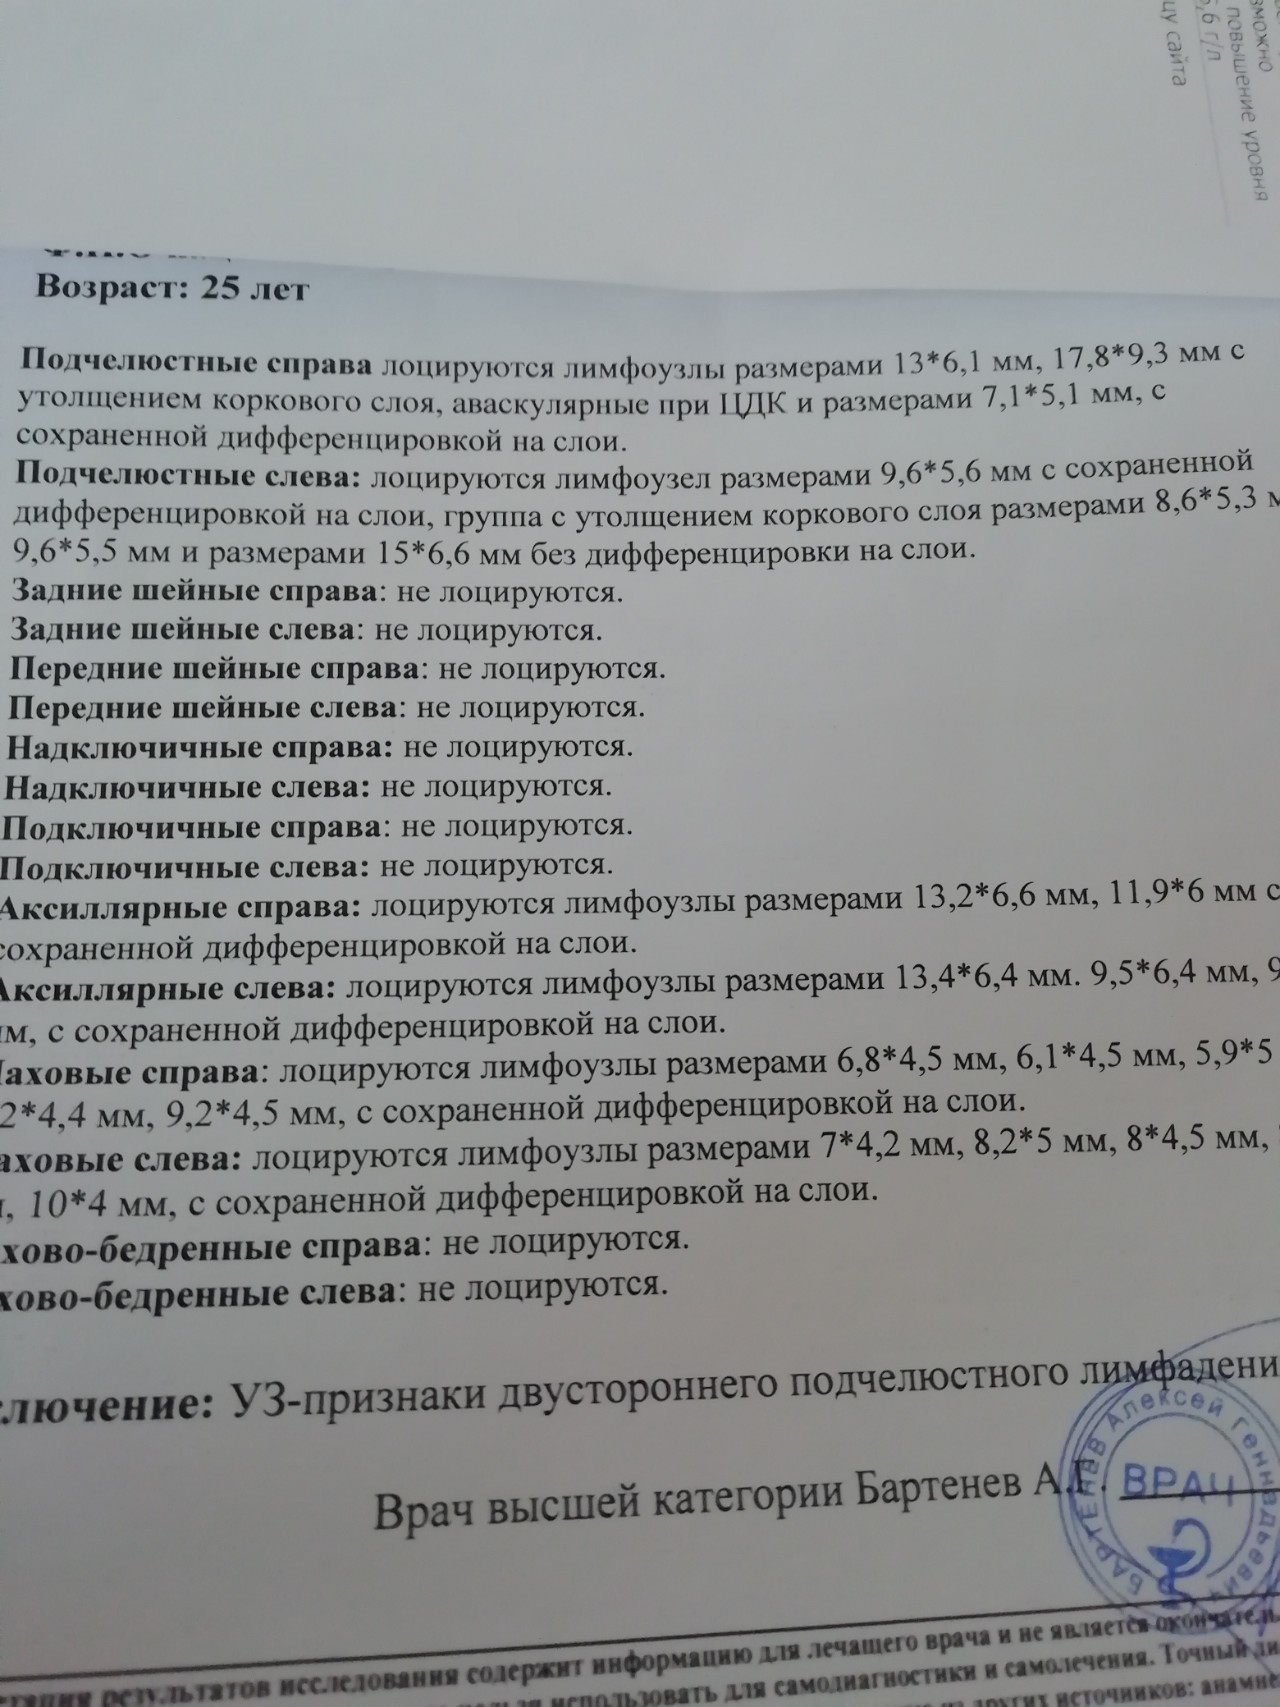

УЗИ лимфоузлов при лимфоме Ходжкина

Раздел: Образы вокруг